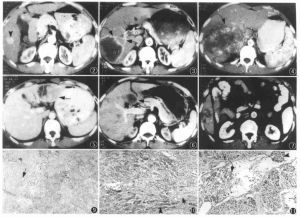

3.CT表現:平掃可見腎局部隆起,內部密度不均勻偏低,其內可見斑片或小點狀鈣化,有時呈蛋殼狀;增強掃描後正常部分腎增強明顯,而癌內增強較低,內部增強程度不規則,有更低密度的壞死區存在。癌可穿破包膜進入腎周脂肪層,晚期穿破腎筋膜擴散至腎外組織。腎細胞癌分期多採用Robson分期法,即Ⅰ期癌限於腎包膜內;Ⅱ期癌已穿破包膜,侵入脂肪層,仍局限在腎筋膜內;Ⅲ期癌已侵入腎靜脈或(和)下腔靜脈,局部淋巴結可能有轉移;Ⅳ期癌已穿破腎筋膜,侵入鄰近臟器或發生遠處轉移。

透片4.MR表現:在多體位觀察了解腫瘤侵犯範圍,略勝CT一籌。隨著腔內泌尿外科的發展,輸尿管鏡檢查可用於上尿路移行細胞癌的診斷及治療。可直接觀察和作組織活檢,也可切除腫瘤。